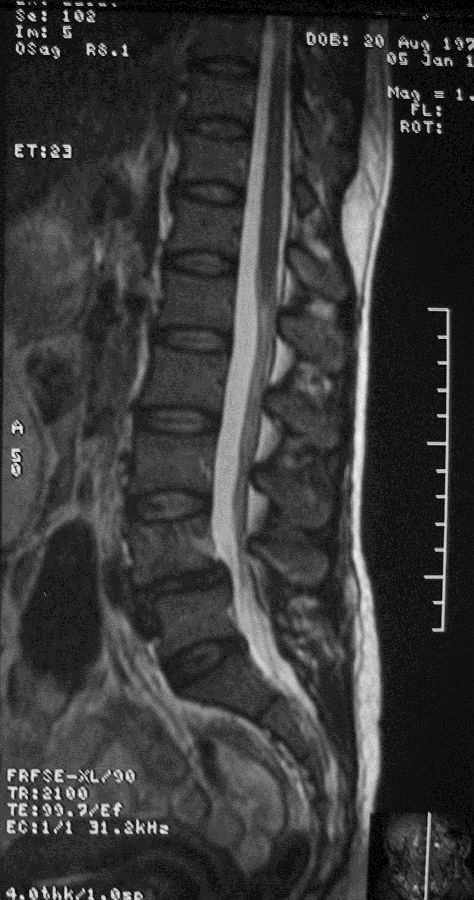

- 王某某,女,63岁,反复腰痛10年

- 3个月前加重并出现右侧臀部疼痛,沿右侧大腿、小腿后侧及外侧放射,右侧为甚,伴间歇性跛行(50米)。

- 体查: L4/5及右髋部压叩痛,右下肢感觉减退,右髋关节活动明显受限,双侧直腿抬高及加强试验(-),右侧4字征(+),右侧托马斯征(+)

- 诊断:L4/5滑脱症合并右侧髋关节OA

- 治疗:先行脊柱减压融合,2年后行右侧THA,随访疗效满意。